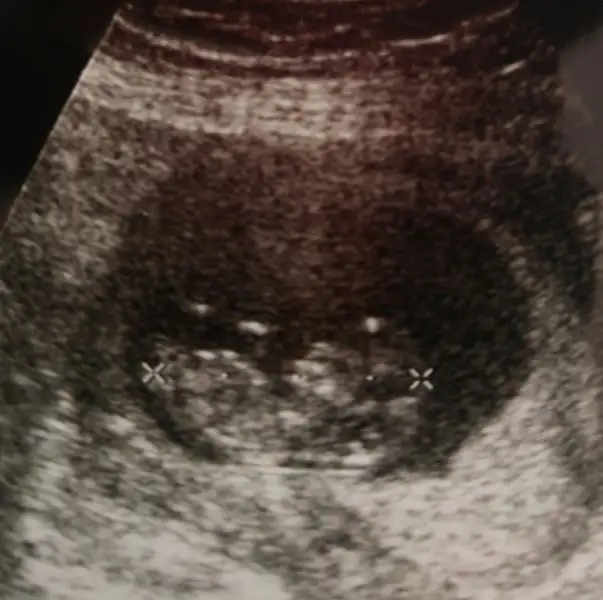

Son kontrolde sabah erken olunca aç gittim ama o kadar oynaktı ki takla atıyorduEvet canım ben oğlumdan önce 2 düşük oğlumdan sonra 1 dış gebelik geçirdim bu sağlıklı Allah a şükür inşallah sağ salim kavuşuruz hepimiz :) ben en son 8+4 de gittim. Haftaya perşembe gidicem ben de kontrole inşallah umarım bir cinsiyet tahimini yapar ya çikolata yicem yine de :))